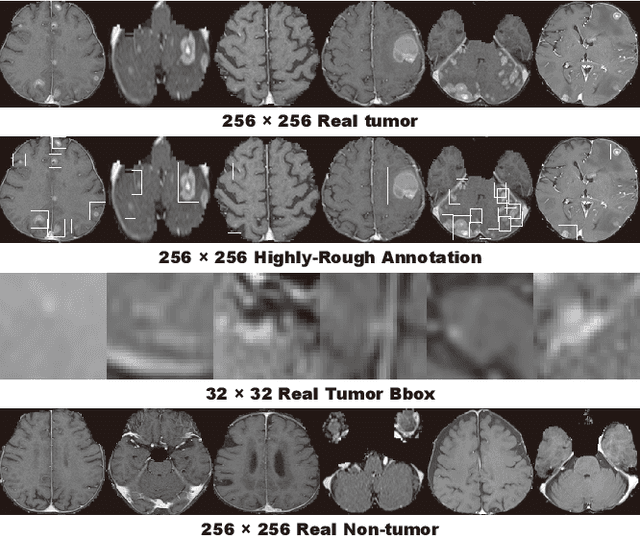

Abstract:Convolutional Neural Network (CNN)-based accurate prediction typically requires large-scale annotated training data. In Medical Imaging, however, both obtaining medical data and annotating them by expert physicians are challenging; to overcome this lack of data, Data Augmentation (DA) using Generative Adversarial Networks (GANs) is essential, since they can synthesize additional annotated training data to handle small and fragmented medical images from various scanners--those generated images, realistic but completely novel, can further fill the real image distribution uncovered by the original dataset. As a tutorial, this paper introduces GAN-based Medical Image Augmentation, along with tricks to boost classification/object detection/segmentation performance using them, based on our experience and related work. Moreover, we show our first GAN-based DA work using automatic bounding box annotation, for robust CNN-based brain metastases detection on 256 x 256 MR images; GAN-based DA can boost 10% sensitivity in diagnosis with a clinically acceptable number of additional False Positives, even with highly-rough and inconsistent bounding boxes.

Abstract:Accurate computer-assisted diagnosis can alleviate the risk of overlooking the diagnosis in a clinical environment. Towards this, as a Data Augmentation (DA) technique, Generative Adversarial Networks (GANs) can synthesize additional training data to handle small/fragmented medical images from various scanners; those images are realistic but completely different from the original ones, filling the data lack in the real image distribution. However, we cannot easily use them to locate the position of disease areas, considering expert physicians' annotation as time-expensive tasks. Therefore, this paper proposes Conditional Progressive Growing of GANs (CPGGANs), incorporating bounding box conditions into PGGANs to place brain metastases at desired position/size on 256 x 256 Magnetic Resonance (MR) images, for Convolutional Neural Network-based tumor detection; this first GAN-based medical DA using automatic bounding box annotation improves the robustness during training. The results show that CPGGAN-based DA can boost 10% sensitivity in diagnosis with an acceptable amount of additional False Positives---even with physicians' highly-rough and inconsistent bounding box annotation. Surprisingly, further realistic tumor appearance, achieved with additional normal brain MR images for CPGGAN training, does not contribute to detection performance, while even three expert physicians cannot accurately distinguish them from the real ones in Visual Turing Test.